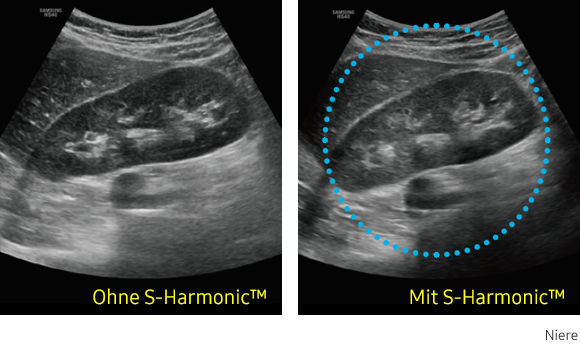

S-Harmonic

Diese neue Harmonic-Imaging-Technologie bietet Ihnen homogene Ultraschallbilder vom Nah- bis zum Fernfeld bei gleichzeitiger Rauschunterdrückung. Kombiniert mit den S-Vue™-Sonden und der S-Vision™ Imaging Engine erzeugt die HS40 Bilder in hoher Qualität.

Ultraschallbild Niere links ohne S-Harmonic und rechts mit S-Harmonic. Ultraschallbild Niere links ohne S-Harmonic und rechts mit S-Harmonic. Ultraschallbild Niere links ohne S-Harmonic und rechts mit S-Harmonic. Ultraschallbild Niere links ohne S-Harmonic und rechts mit S-Harmonic.